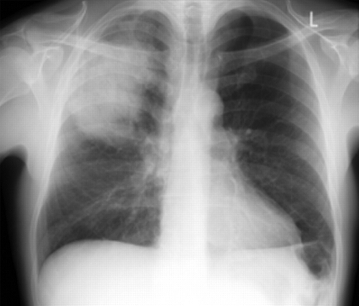

Pneumonia adquirida na comunidade em adultos

Radiografia de tórax posteroanterior mostrando consolidação do lobo superior direito em um paciente com pneumonia adquirida na comunidade

Durrington HJ, et al. Recent changes in the management of community acquired pneumonia in adults. BMJ 2008;336:1429.